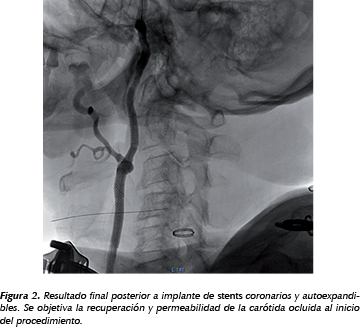

Revista Gastro NÂș70 By Revista Gastro Issuu